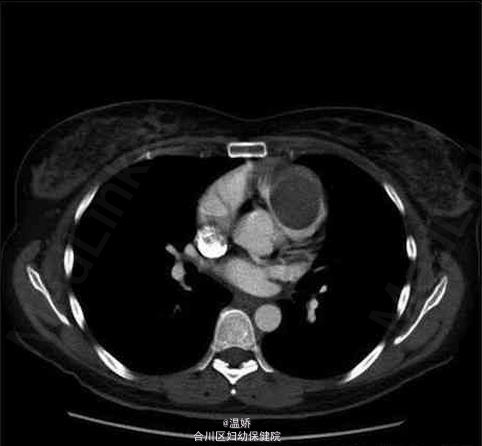

一例罕见的心室粘液瘤

粘液瘤

患者,女,42岁